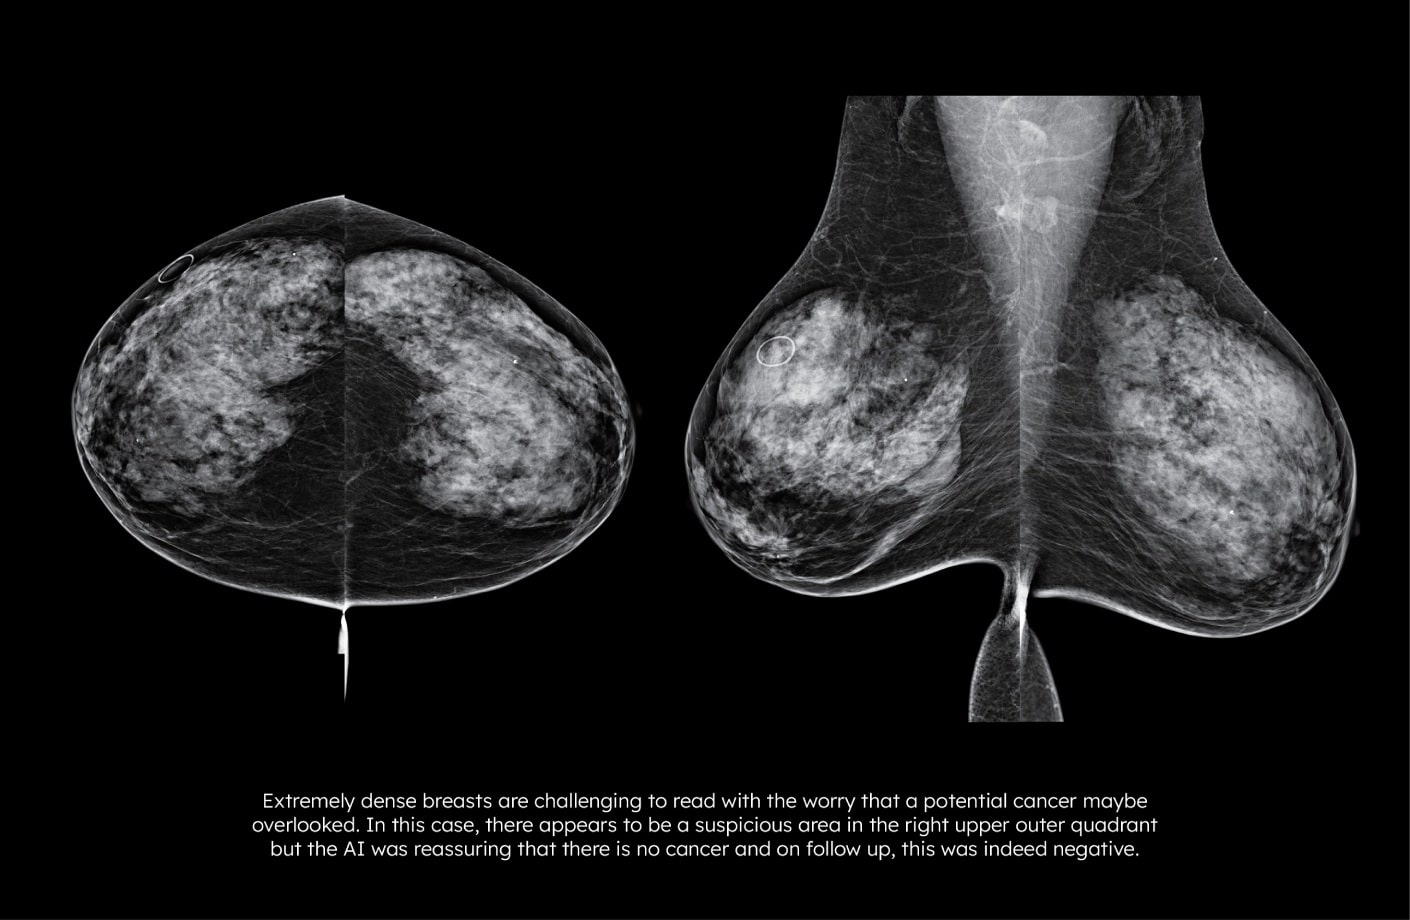

루닛 인사이트 MMG는 특이도 향상5을 통해 위양성 및 불필요한 재검 감소에 도움을 주는 것으로 나타났습니다.